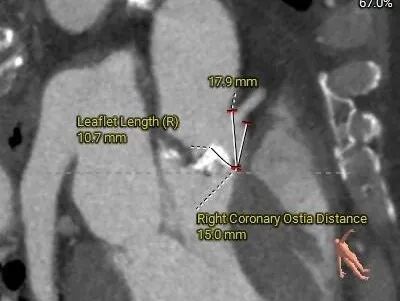

术前CT评估

Type0型二叶式主动脉瓣,LVOT偏敞口型,非横位心。

重度钙化,HU 850积分1711mm3。

左冠18.8,右冠19,综合分析冠脉阻挡风险适中。

瓣上多平面分析。